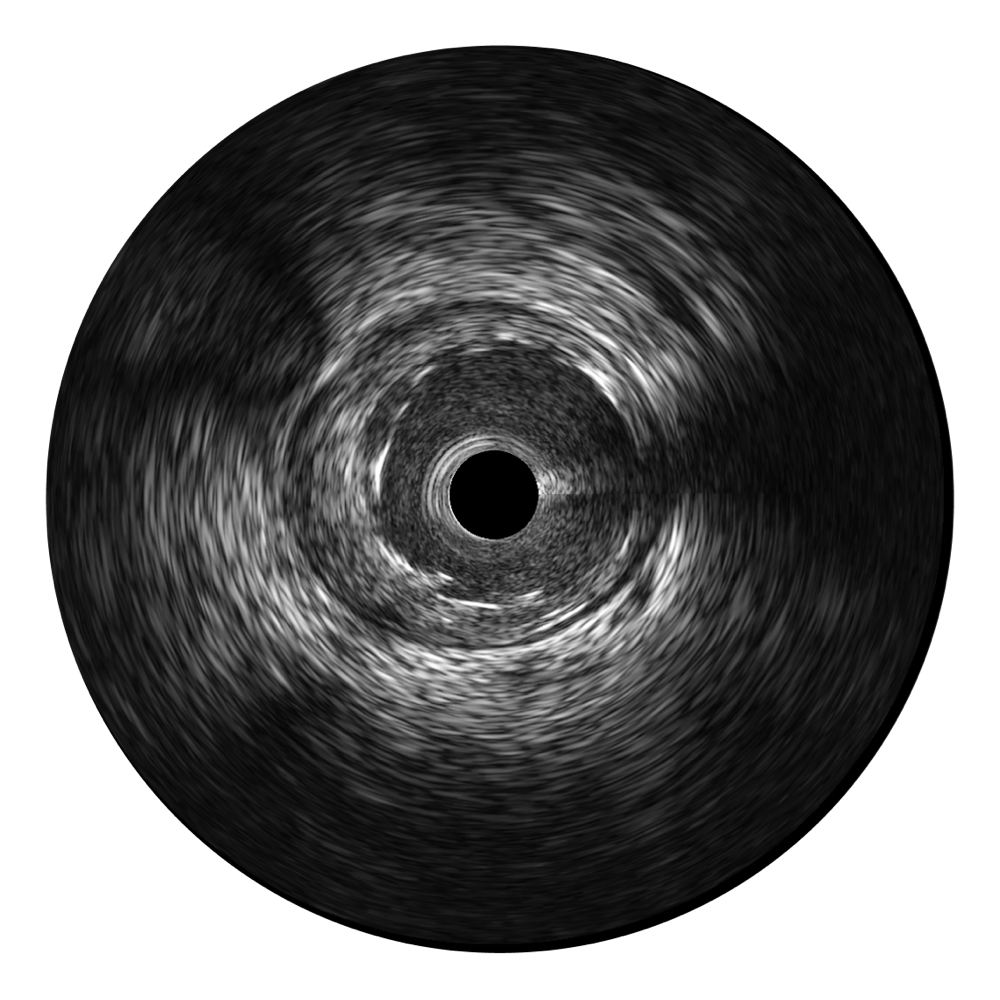

• milan米兰宽频IVUS图像

• 传统IVUS图像

对比传统IVUS导管成像,milan米兰宽频IVUS图像的近场支架梁显影更细腻,远场中膜外血管仍清晰可辨,兼顾远中近,兼顾分辨力与穿透深度